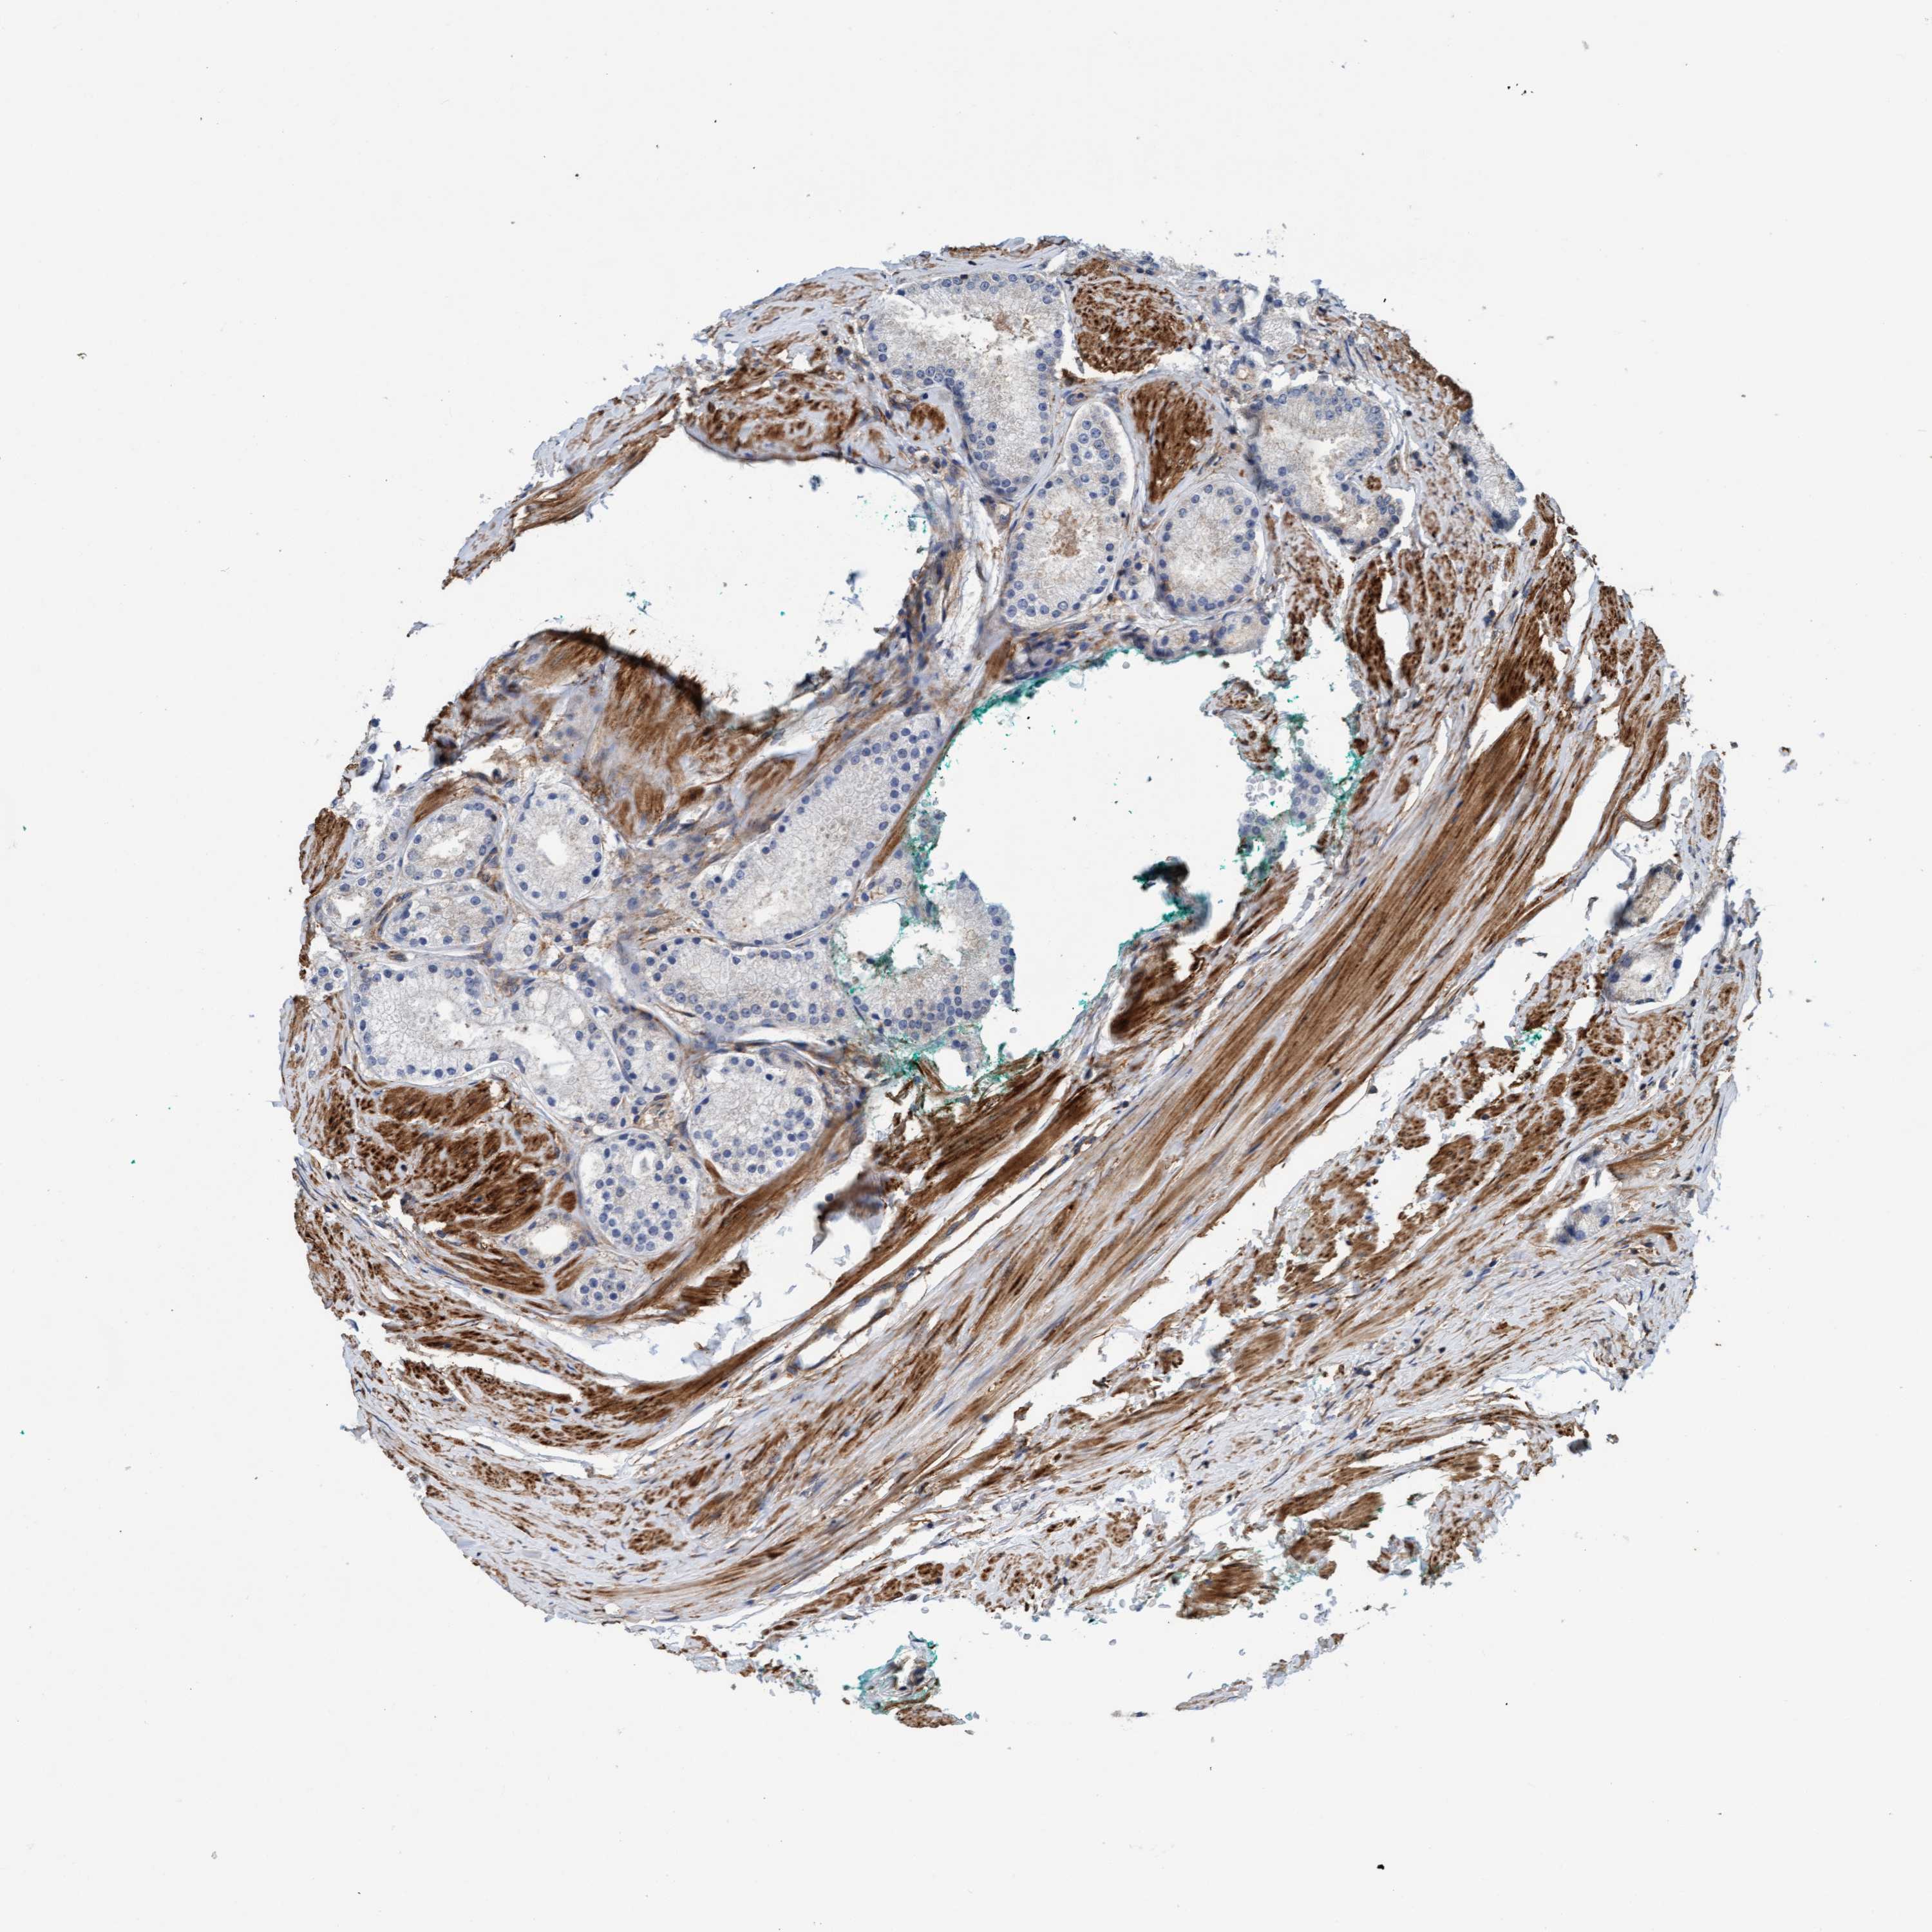

PROSTATE CANCER - Protein expressioni

A mouse-over function shows sample information and annotation data. Click on an image to view it in a full screen mode. Samples can be filtered based on level of antibody staining by selecting one or several of the following categories: high, medium, low and not detected. The assay and annotation is described here.

Antibody stainingi

Antibody staining in the annotated cell types in the current human tissue is reported as not detected, low, medium, or high, based on conventional immunohistochemistry profiling in selected tissues. This score is based on the combination of the staining intensity and fraction of stained cells.

Each image is clickable and will lead to virtual microscopy that enables deeper exploration of all samples and also displays staining intensity scores, fraction scores and subcellular localization as well as patient and tissue information for each sample.

Antibody HPA002552

Antibody HPA023201

Staining

High

Medium

Low

Not detected

Intensity

Strong

Moderate

Weak

Negative

Quantity

>75%

75%-25%

<25%

None

Location

Nuclear

Cytoplasmic/membranous

Cytoplasmic/membranous,nuclear

Adenocarcinoma, Low grade

Adenocarcinoma, Medium grade

Adenocarcinoma, High grade